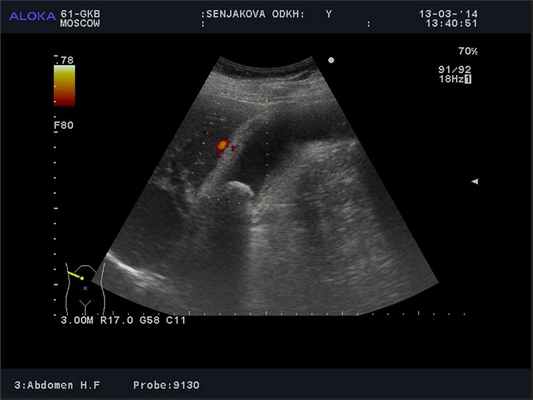

Наиболее информативно при остром холецистите, как и вообще при желчекаменной болезни - ультразвуковое исследование. Картина достаточно типичная: увеличение желчного пузыря, утолщение его стенки за счет отека, желчного пузыря, наличие жидкостных скоплений вокруг пузыря, признаков деструкции стенки

Ультразвуковая картина острого холецистита: увеличенный желчный пузырь, с отечной стенкой, блокирующий конкремент в шейке. При допплерографии определяется усиление кровотока в стенке желчного пузыря

Чаще всего УЗИ достаточно для определения тактики лечения, в редких случаях мы используем компьютерную томографию или МРТ – последнюю чаще для исключения патологии желчевыводящих протоков (холедохолитиаза и т.д.), что влияет на тактику лечения таких пациентов.